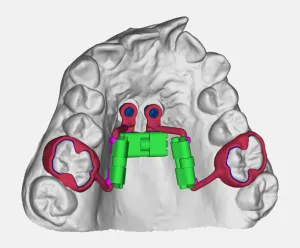

Espansore Tooth Borne

L'espansore Tooth Borne è un dispositivo ortodontico progettato per espandere il palato attraverso l'ancoraggio dentale. Realizzato con tecnologia CAD-CAM, garantisce precisione unica e comfort ottimale per il paziente.